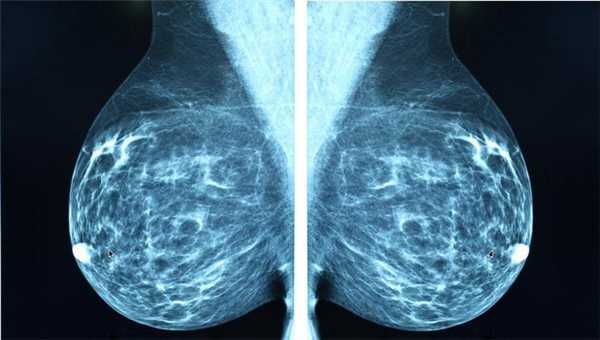

Маммография

Отдельный вид рентгенографии, разработанный для диагностики заболеваний молочной железы, поэтому проходят маммографию женщины. О рекомендуемом возрасте для проведения процедуры единого мнения нет. Маммография помогает убедиться в отсутствии злокачественной опухоли с точностью до 89%. Считается, что женщины должны проходить обследования регулярно, начиная с 39 лет, хотя некоторые онкологические сообщества рекомендуют обследоваться с более молодого возраста.

Маммографию назначают для диагностики рака молочной железы, процедура проходит быстро, это плюс, но пациентку облучают, а риск неверного диагноза остаётся, это минус. Маммография может быть цифровой и плёночной, цифровая маммография обеспечивает получение более чёткого снимка.

Классический рентген по-прежнему остаётся важным методом для диагностики самых разных заболеваний. Например, маммография (рентгеновское исследование молочных желез) - лучший способ скрининга рака молочной железы. Возможности КТ в выявлении злокачественных и воспалительных процессов в этом органе существенно ниже.

- рак молочной железы;